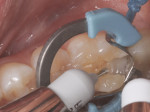

A patient presented with decay on the distal aspect of tooth No. 30 that necessitated a direct composite restoration. The patient was administered a 2% lidocaine solution containing 1:100,000 concentration of epinephrine to achieve an inferior alveolar nerve block. Once comfortable, a 330 carbide bur was used to prepare the distal-occlusal surfaces of the tooth. Decay was removed using a round No. 4 bur and confirmed by the use of a caries indicating solution (Figure 1). The preparation was isolated with the Palodent® Plus Sectional Matrix System (DENTSPLY, www.dentsply.com) by using the subgingival molar matrix band, universal ring, and wedge. In place of a rubber dam, proper suctioning and use of a cotton roll prevented salivary contamination to help achieve an optimal clinical result. A 2% chlorhexidine solution, acting as a disinfectant, was blotted into the preparation and then lightly suctioned.